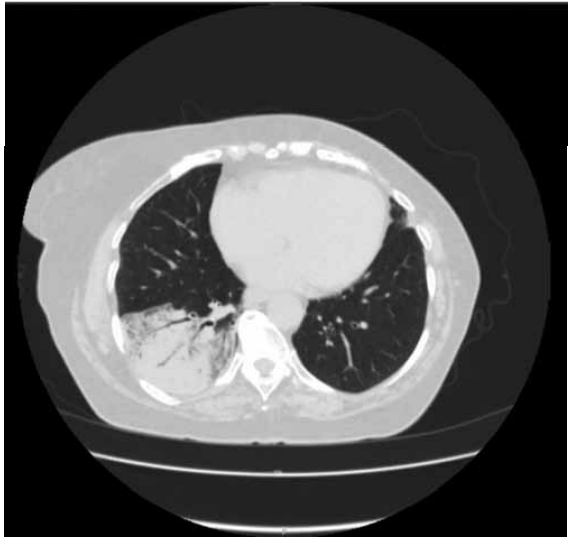

Uma paciente procura auxílio médico com uma queixa de tosse seca há 1 semana. Tem antecedente de hipertensão arterial. Entretanto, há muito tempo não procura controle médico. Ela costuma medir sua pressão arterial por meio de um esfigmomanômetro de pulso. Quando estava normal, não fez uso de hidroclorotiazida 25 mg. Regularmente toma losartana 50 mg à noite e anlodipino 5 mg pela manhã.

Ela realizou uma tomografia computadorizada de tórax:

(Arquivo pessoal; imagem usada com autorização)

Assinale a alternativa correta quanto à prescrição a ser realizada.